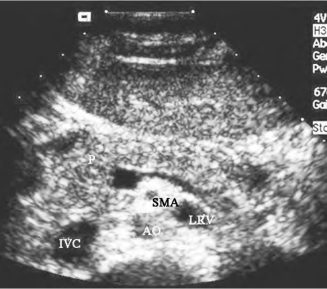

1.36.4四、腹腔大血管